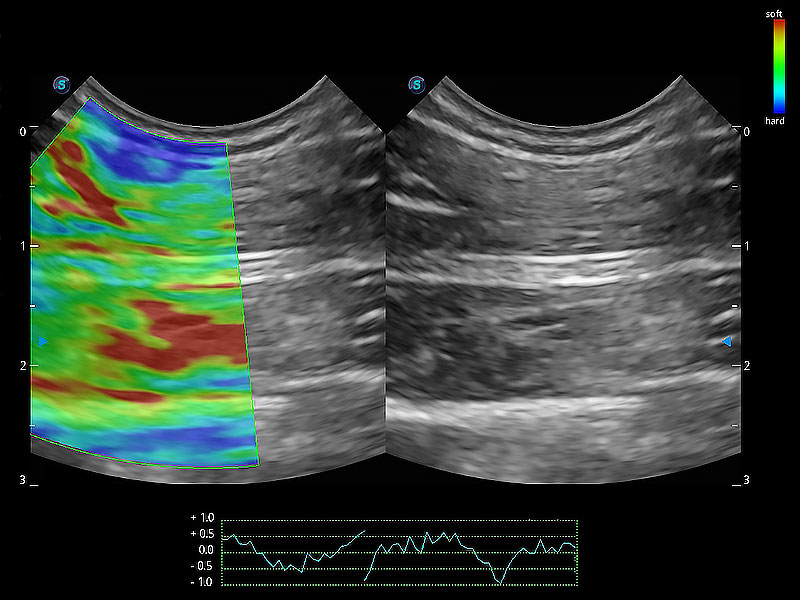

• 應(yīng)變式彈性成像

操作簡便,無需高頻度外力作用即可真實反映組織的形變,快速評估腫瘤良惡性。